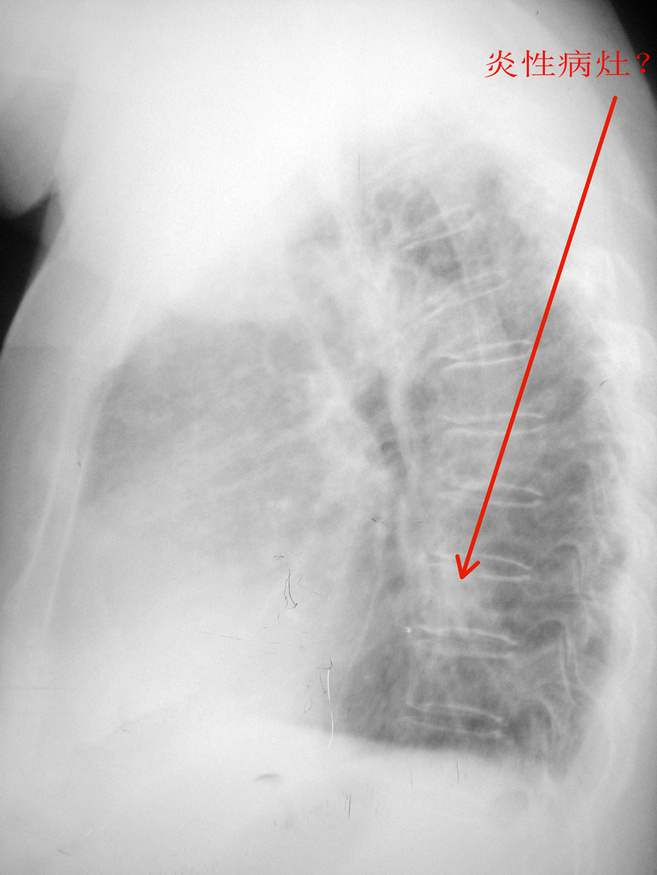

女.80.慢支炎5年.加重1周.请各位会诊

右肺中叶肺不张或阻塞性肺炎+两肺间质纤维化---ct确诊。

考虑慢性支气管炎合并感染,右上继发型肺结核。必要时做ct进一步检查。

右上肺可见片结影,余肺纹增多且模糊,支持慢支并感染,右上肺继发性结核。建议ct。

慢性支气管炎合并感染,双肺上野结核。